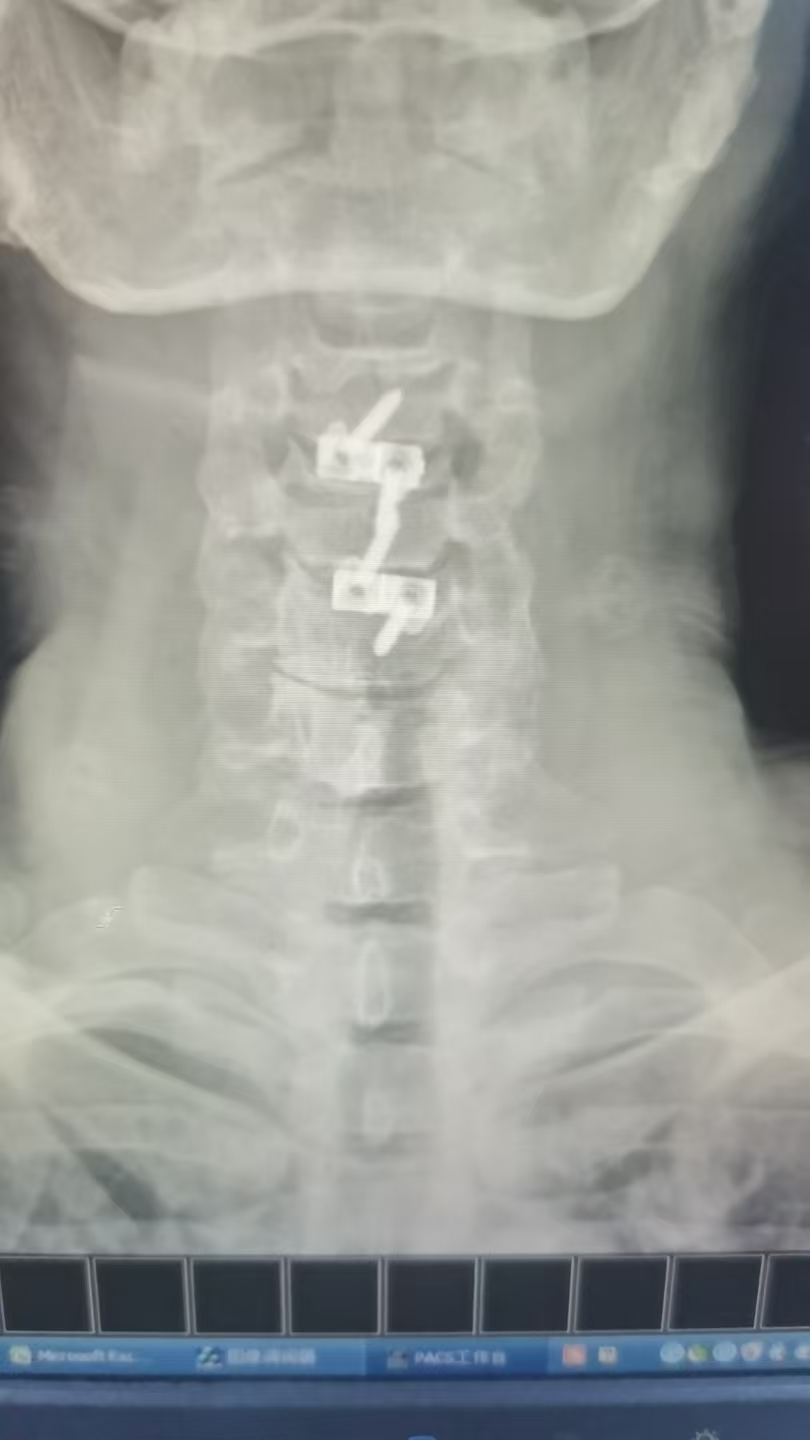

(术后图)

47岁李先生(化名)近日因车祸导致“颈髓损伤,四肢麻木无力”入院。经我院脊柱外科团队详细检查,影像学检查显示颈3/4及4/5节段椎间盘突出,脊髓神经根受压,引发四肢不完全瘫痪。术前右侧上、下肢体肌力:3级,左上肢肌力3级,左下肢肌力1级。

由于保守治疗效果不明显,医护团队综合评估后,决定为患者施行颈椎前路微创手术。在南医三院派驻骨科专家、东凤人民医院副院长闫慧博(挂职)的带领下,我院骨科团队共同为患者实施“颈椎3/4、4/5双节段前路椎间盘摘除+椎体融合术”。